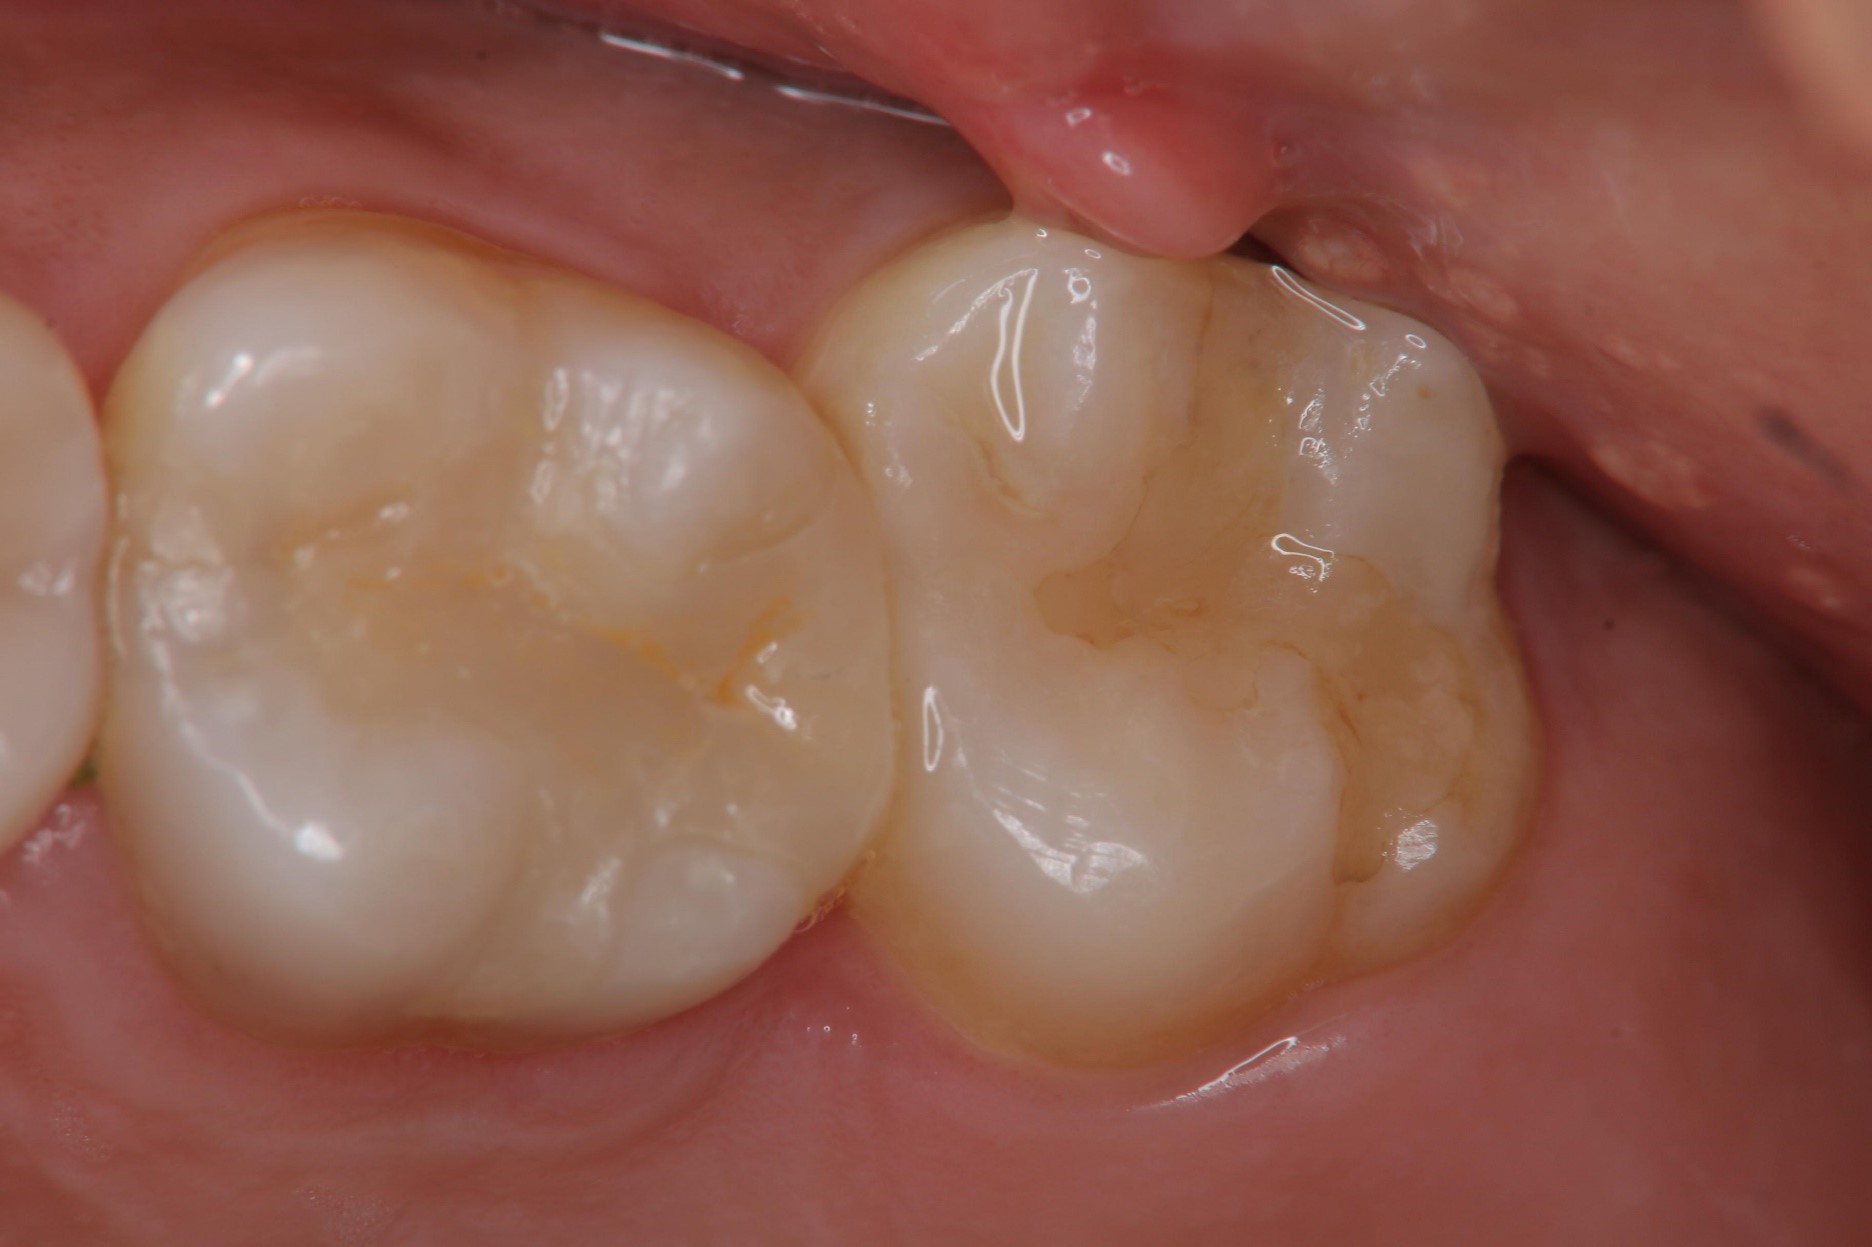

陶瓷崁體

陶瓷崁體邊緣完整

無殘膠存在